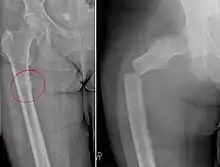

| Chalkstick fracture due to bone metastasis of breast cancer. The left image shows the metastasis, on the right a pathological fracture a few days later. | |

Chalkstick fractures are fractures, typically of long bones, in which the fracture is transverse to the long axis of the bone, like a broken stick of chalk.[1] A healthy long bone typically breaks like a hard woody stick as the collagen in the matrix adds remarkable flexibility to the mineral and the energy can run up and down the growth rings of bone. The bones of children will even follow a greenstick fracture pattern.

Chalkstick fractures are particularly common in Paget's disease of bone, and osteopetrosis.[2] It is also seen in cases of fused spine as in a patient with ankylosing spondylitis.[3]